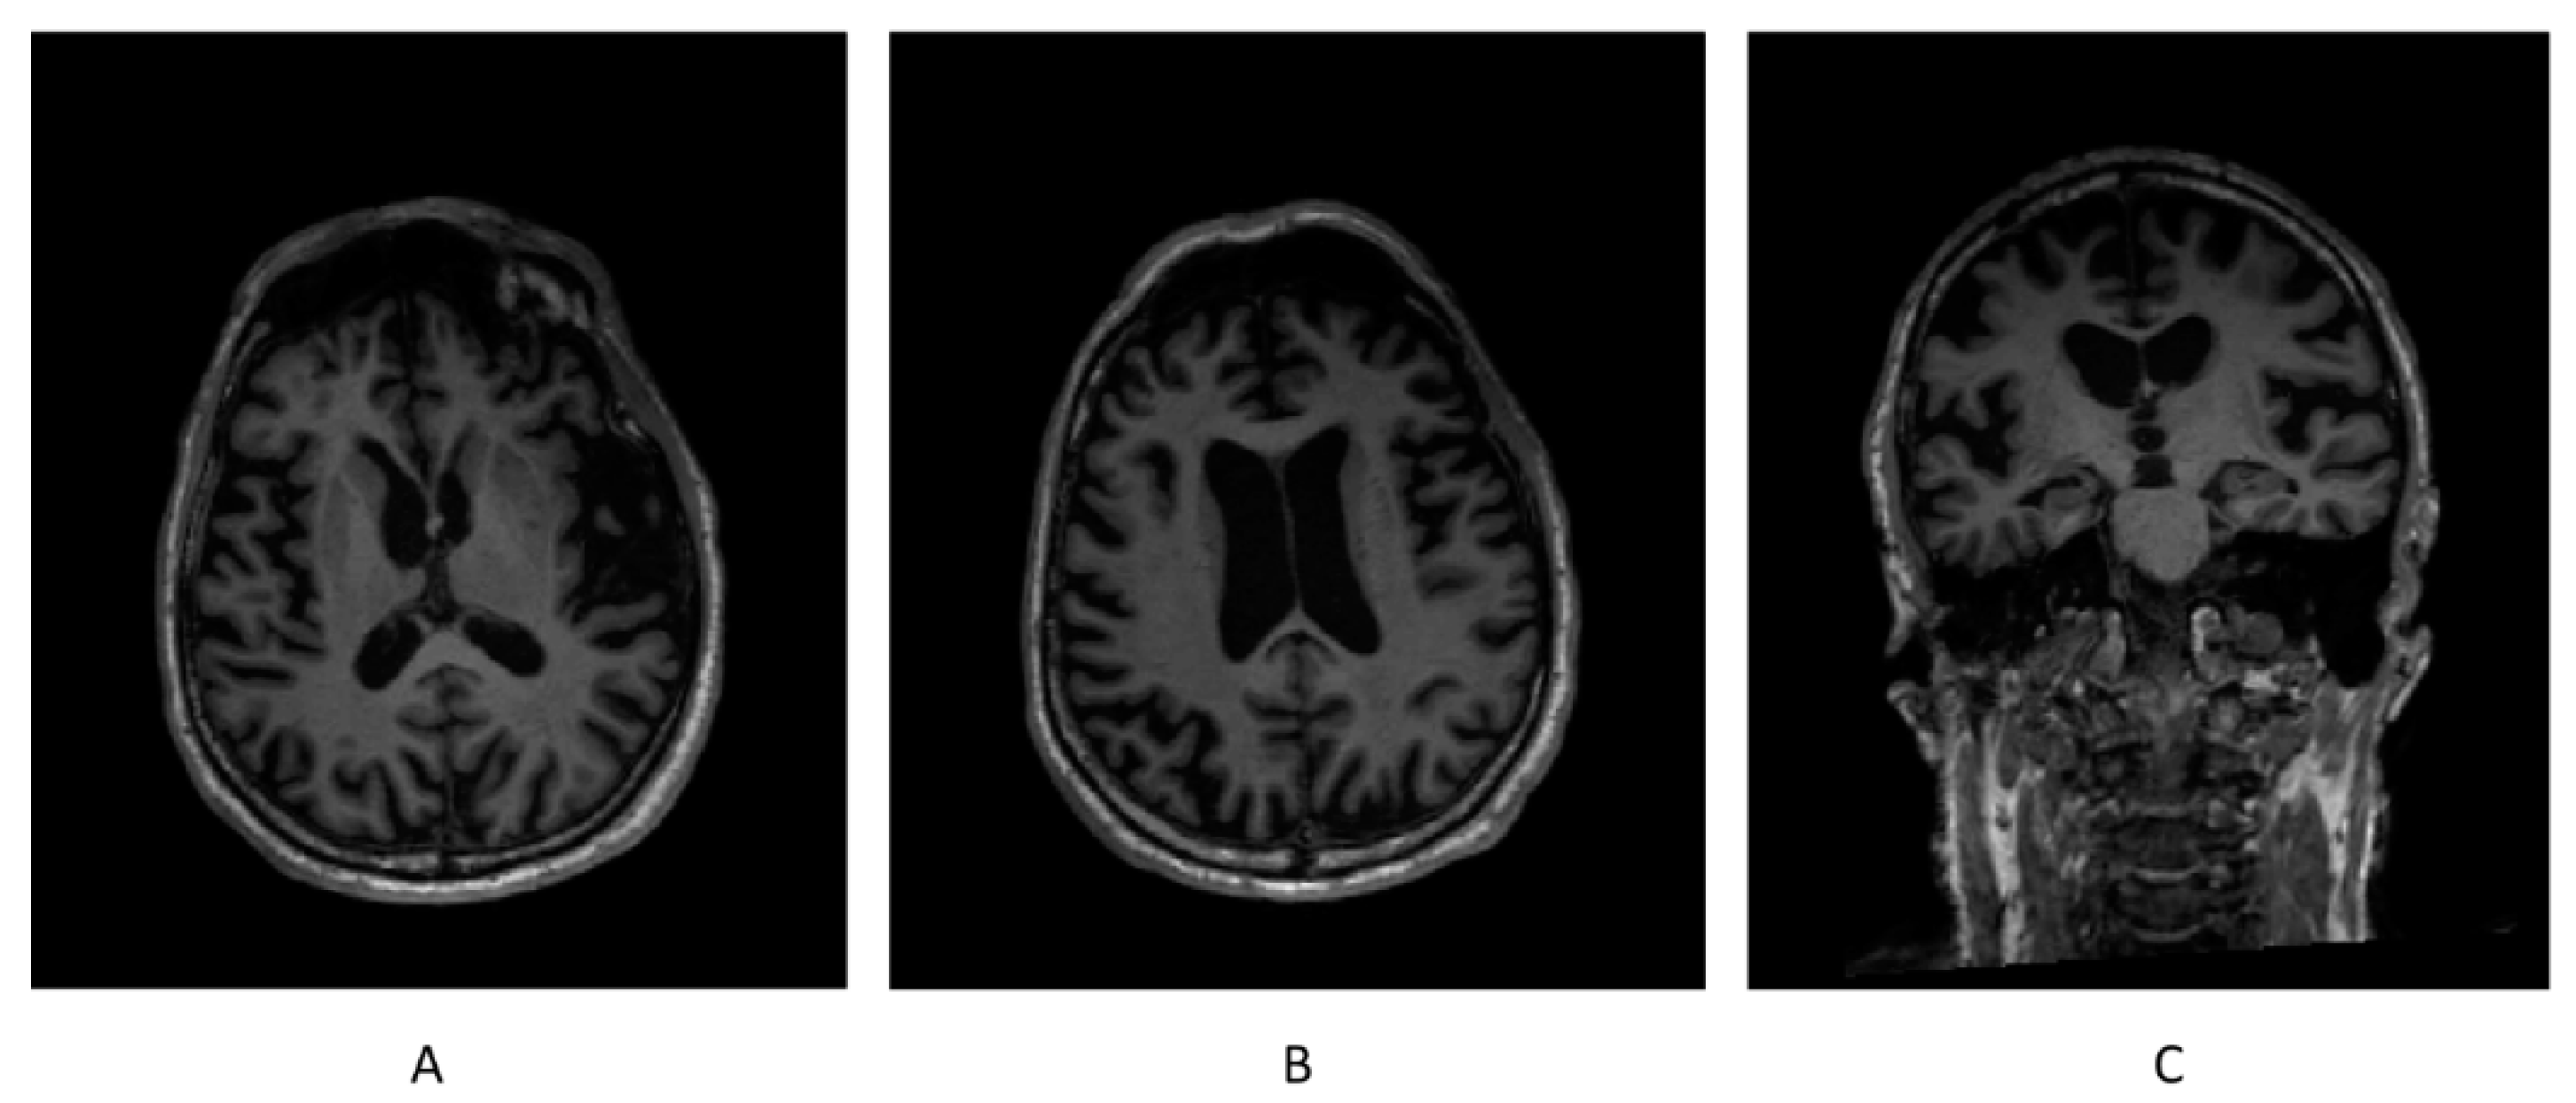

3.5. Brain Morphometry from Structural MRI

Brain morphometry from the structural MRI conducted before the protocol did not find any brain region having a volume out of the normative range. Brain morphometry from the structural MRI attained on 1 October 2021 revealed that the volumes of both gray matter (GM) and white matter (WM) in bilateral frontal lobes were below the normative ranges (TIV-normalized volume of GM in left frontal lobe = 5.28%, and normative range = 5.40–6.59%; TIV-normalized volume of GM in right frontal lobe = 5.28%, and normative range = 5.34–6.46%; TIV-normalized volume of WM in left frontal lobe = 4.07%, and normative range = 4.41–5.67%; and TIV-normalized volume of WM in right frontal lobe = 4.29%, and normative range = 4.37–5.55%), while the volumes of other brain regions were within the normative ranges (Figure 4).

Figure 4.

High-resolution 3D T1-weighted sequence of the structural brain MRI on 1 October 2021. (A) Axial slice displaying normal bilateral basal ganglia, (B) axial slice displaying atrophic bilateral frontal lobes, and (C) coronal slice displaying normal bilateral hippocampus.

The ROIs whose atrophy rates were calculated included both GM and WM in bilateral frontal lobes, bilateral parietal lobes, and bilateral temporal lobes, as well as bilateral insula and bilateral striatum. The atrophy rate of the whole brain was also calculated in contrast with the ROIs. As a result, both the GM and WM in the left frontal lobe, the GM in left parietal lobe and right insula, WM in right frontal lobe, and WM in right parietal lobe showed abnormally high atrophy rates (>4%). Neither the temporal lobes nor striatum had any significant atrophy rate (Table 8).